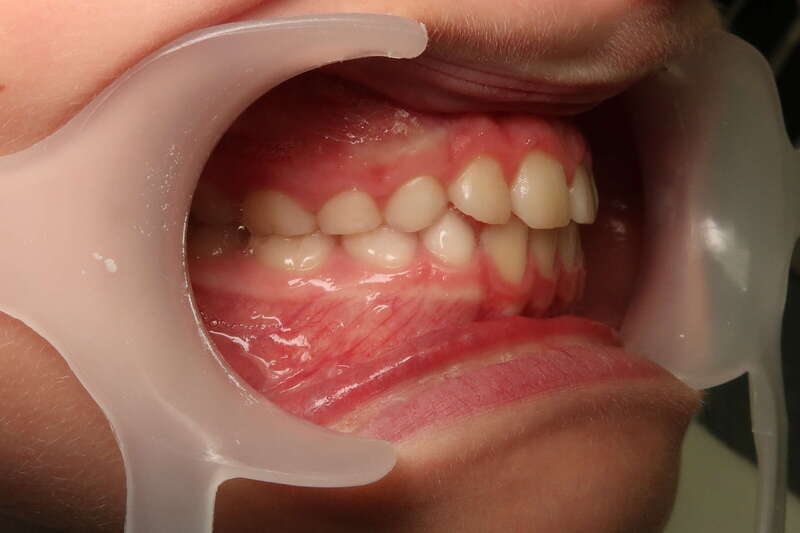

Cas n°1 traité par aligneurs (interception) - enfant

Ce cas d’interception chez un enfant de 8 ans démontre l'efficacité des aligneurs pour corriger des troubles fonctionnels précoces. Le diagnostic présentait des inversions d'articulé provoquant une déviation de la mandibule vers la gauche et un décalage des milieux.

Grâce à une coopération exemplaire et un traitement totalement indolore, l'expansion de l'arcade a permis de recentrer la mâchoire. Cette intervention a littéralement remis la croissance sur les rails, neutralisant le risque d'asymétrie faciale squelettique.